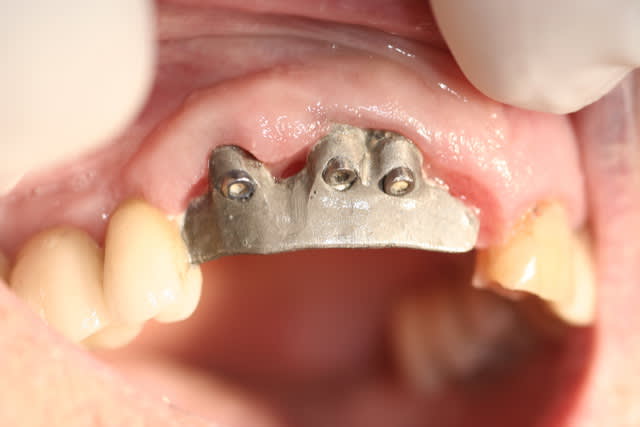

Un "bridge" 22-23-24 a été réalisé il y a 6 ans, sur 2 implants.

Cliniquement, si la 22 a été réalisée de façon classique, 23 et 24 sont montée sur une armature métallique en selle. En palatin, la selle avance sur le palais de 2 mm, mais en vestibulaire, on est plus à 8 mm de recouvrement.

La formation de tartre dans l'intrados de la selle donne une gencive inflammatoire, saignant spontanément au passage d'un fouloir rond. Je vous laisse voir les photos.